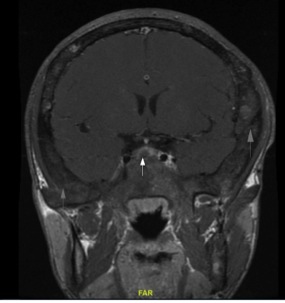

- МРТ головного мозга с внутривенным контрастированием: Аденома гипофиза с супраселлярным распространением. МР-картина фиброзной остеодисплазии. Субтотальное сужение наружных слуховых проходов, сужение зрительных каналов на уровне верхней глазничной щели (рис. 10, 11).

Рис. 10. МРТ головного мозга пациента И. Аденома гипофиза (белая стрелка).

Описание. Полость турецкого седла деформирована — сужена в переднезаднем размере. В полости турецкого седла, в супраселлярной цистерне имеется солидное объемное образование неоднородной структуры, размерами 9×16×9 мм. Образование смещает и компримирует хиазму.

Рис. 11. МРТ головного мозга пациента И. Очаги фиброзной дисплазии в затылочной кости (серая стрелка).

Описание. Асимметричная деформация костей черепа, преимущественно лицевого черепа, деформация костей основания черепа, выраженная деформация затылочной кости (серая стрелка), деформация тела и крыльев клиновидной кости; имеется полная облитерация лобных пазух, правой верхнечелюстной пазухи, пазух основной кости, частичная облитерация решетчатой кости, левой верхнечелюстной пазухи, сужение наружных слуховых проходов. Структура костей изменена по типу фиброзной дисплазии.